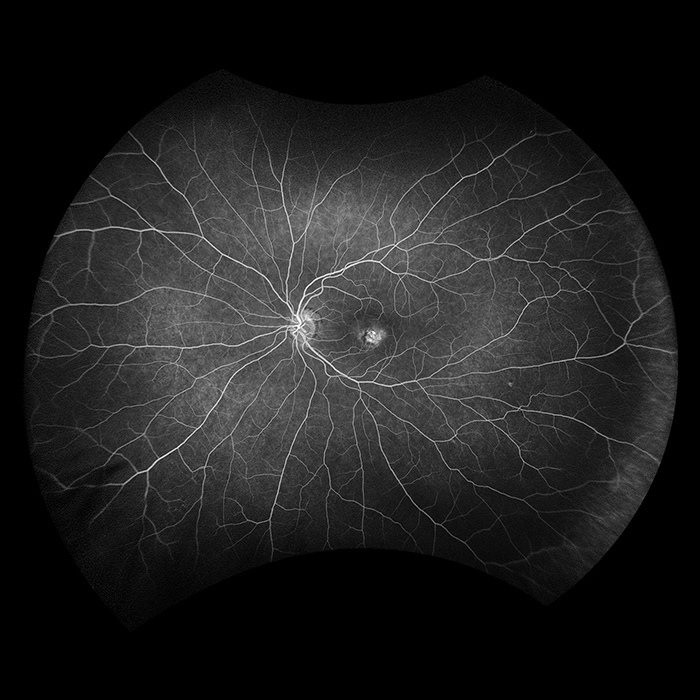

- Fluoreszenzangiographie